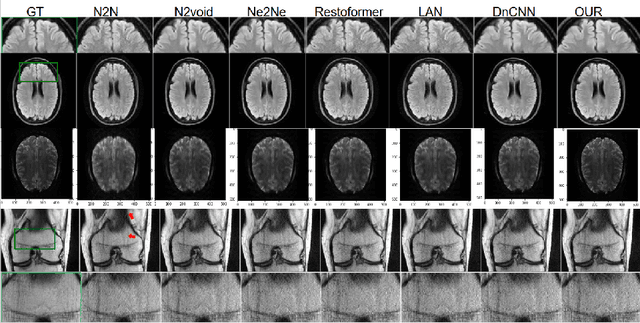

Abstract:Medical image denoising is essential for improving the reliability of clinical diagnosis and guiding subsequent image-based tasks. In this paper, we propose a multi-scale approach that integrates anisotropic Gaussian filtering with progressive Bezier-path redrawing. Our method constructs a scale-space pyramid to mitigate noise while preserving critical structural details. Starting at the coarsest scale, we segment partially denoised images into coherent components and redraw each using a parametric Bezier path with representative color. Through iterative refinements at finer scales, small and intricate structures are accurately reconstructed, while large homogeneous regions remain robustly smoothed. We employ both mean square error and self-intersection constraints to maintain shape coherence during path optimization. Empirical results on multiple MRI datasets demonstrate consistent improvements in PSNR and SSIM over competing methods. This coarse-to-fine framework offers a robust, data-efficient solution for cross-domain denoising, reinforcing its potential clinical utility and versatility. Future work extends this technique to three-dimensional data.